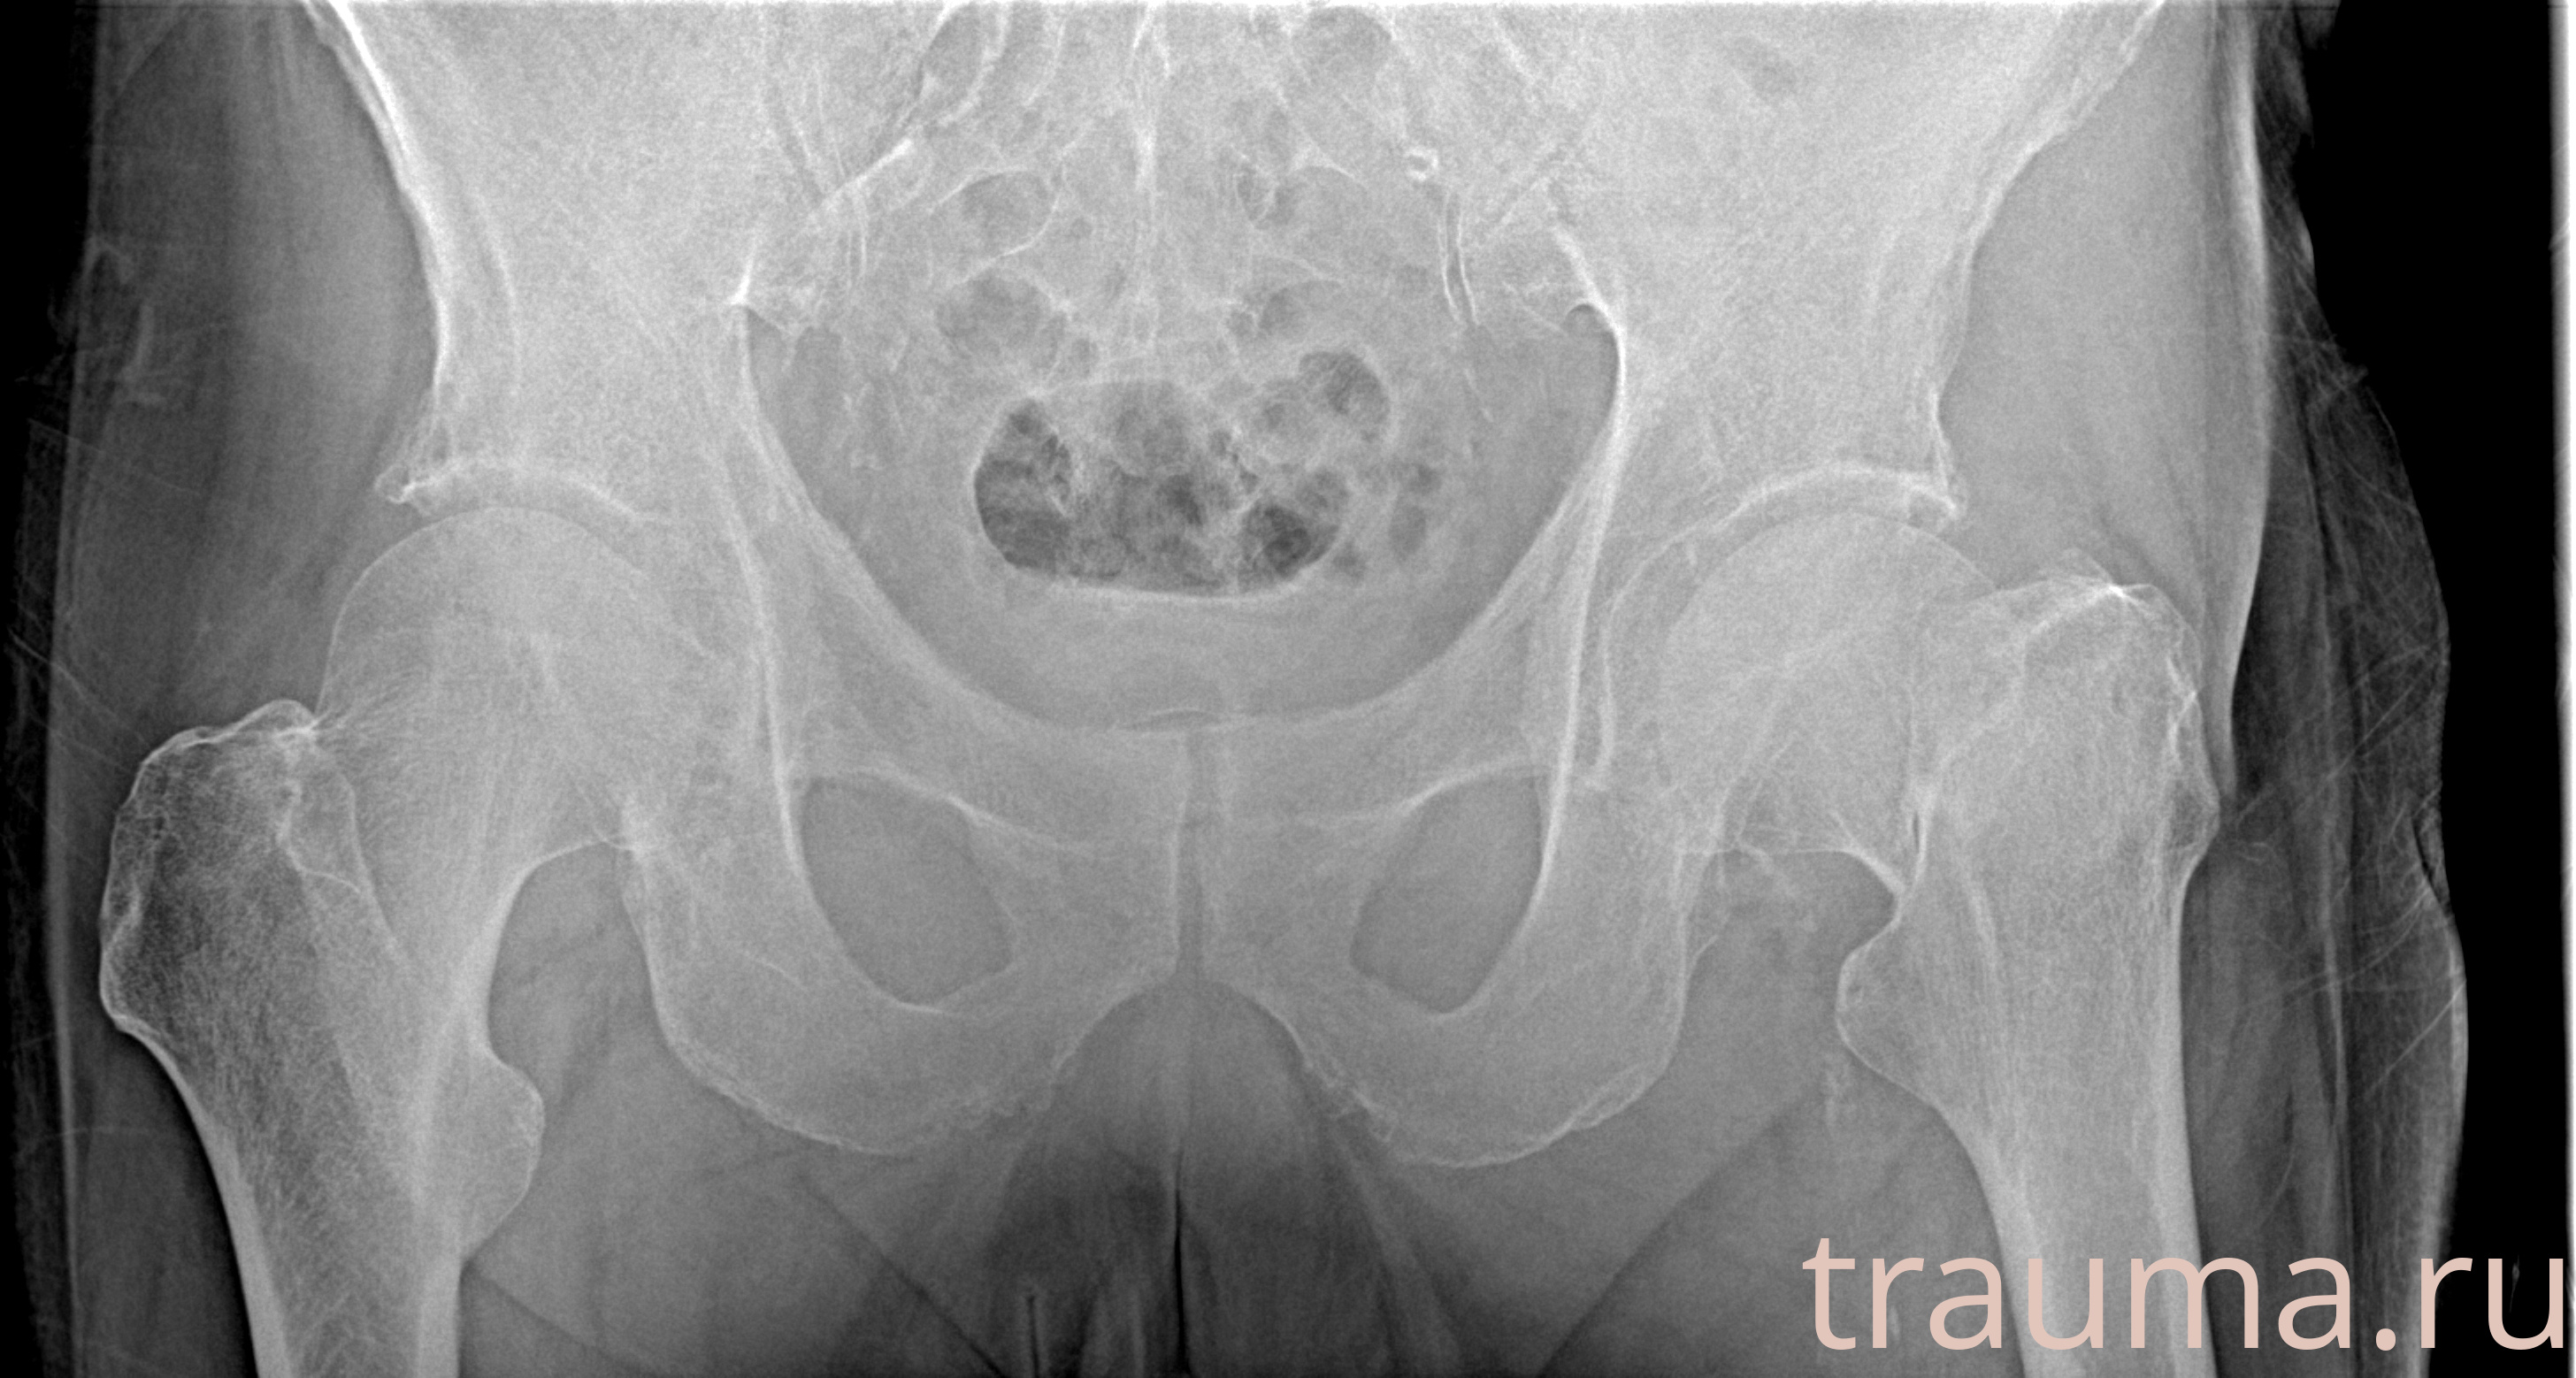

Рентгенограммы

Рентген на дому: по вашему адресу приезжает врач-рентгенолог, травматолог-ортопед с мобильным рентгеновским аппаратом, проводит диагностику травмы или заболевания, делает необходимые рентгенограммы, дает рекомендации по дальнейшему лечению. Получить качественные снимки в домашних условиях возможно благодаря уникальной методике, разработанной МосРентген Центром для института  Склифосовского